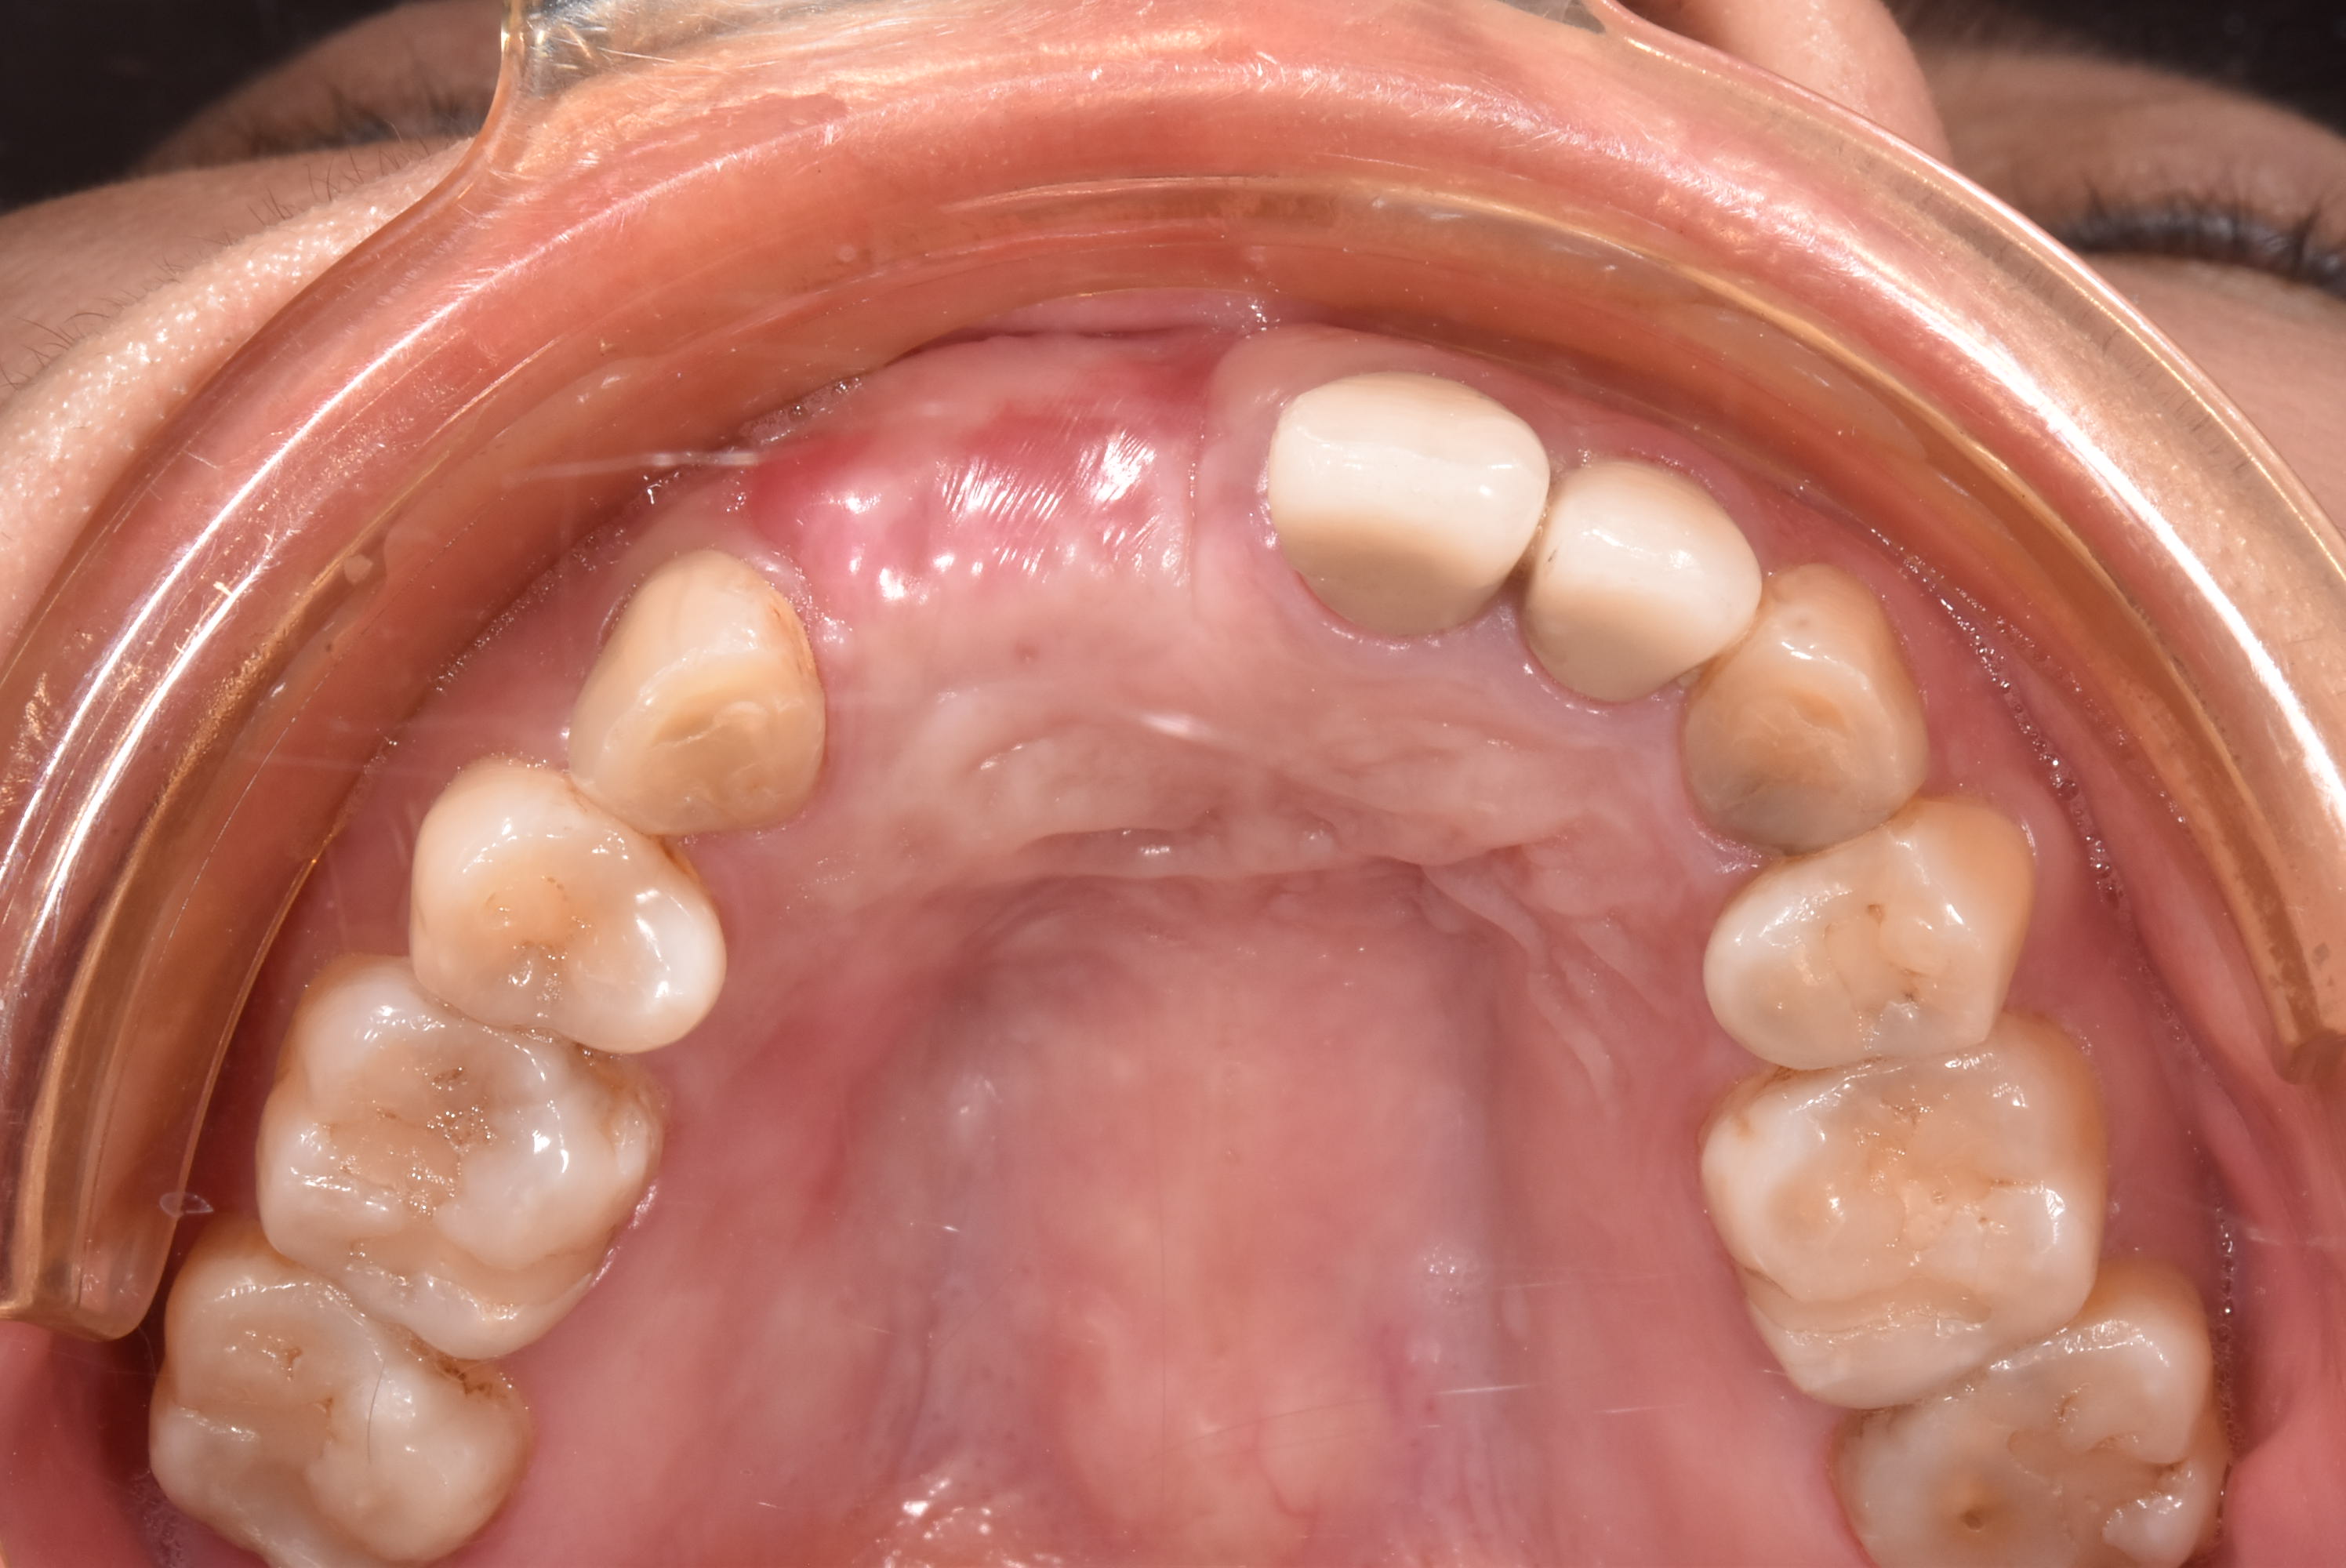

牙齦移植術(補肉)

手術案例

術前加術後案例

案例三